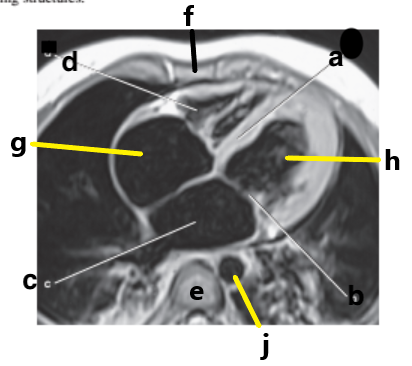

What is letter a ?

Left Ventricle

Left atrium

Right ventricle

What is letter h ?

What is letter d ?

What is letter e ?

Vertebral body

What is letter g ?

Right atrium